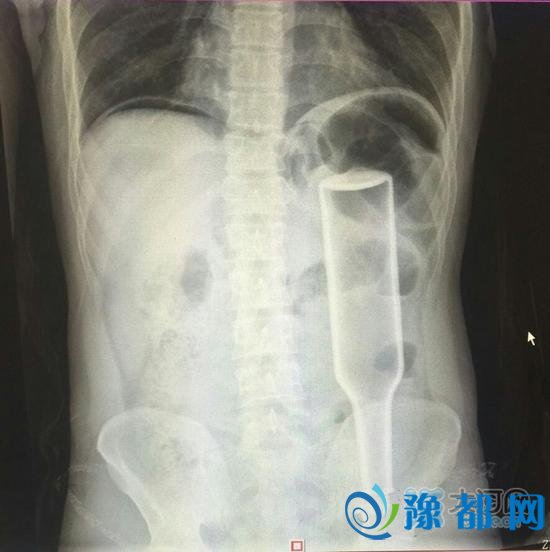

看这片子,花露水瓶子已经很“深入”了。

从检查片来看,瓶子已经塞到了他的直肠和乙状结肠的交界处,这是一个拐角处,瓶子死死地卡在这里,且显示右侧膈下有游离气体,提示消化道穿孔,张春礼大夫判断王某左侧大肠穿孔,于是当即联系手术室实施急诊手术。